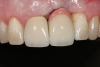

Fig 2. Final restoration at 2 years resulting in gray “show-through” and a compromised esthetic result.

Figure 2

In the case presented in Figure 1 and Figure 2, the author based the decision to restore a badly compromised maxillary central incisor on his clinical experience and the patient's desire to keep the tooth, and while the restoration lasted several years, the esthetic result turned out to be poor due to the gray show-through at the gingival area and deep below the tissue from the root (Figure 2). The literature has indicated that this dark discoloration may be due to the use of certain intracanal medicaments during the root canal procedures, including some antibiotic pastes and/or liquids, or possibly the previous use of metallic restorative material in the canal.7,8 Removal of this discoloration is difficult and Zimmerli et al showed in a literature review that different bleaching techniques offer limited success and a high incidence of the discoloration returning.9

There are two important points that can be gleaned from this case when considering the restoration of compromised teeth. The first is whether the esthetic failure caused by the gray show-through could have been avoided if the tooth had been replaced with a dental implant. If the darkness was caused by the discolored root, the better option may have been to extract the tooth and graft the site; with thickened tissue and adequate bone, an implant may have been able to have been placed without any residual dark show-through. And secondly, how much should patients' desires influence, or even dictate, treatment options? While these questions may never be definitively answered, there are several criteria based on sound research that are crucial in a clinician's decision-making process.